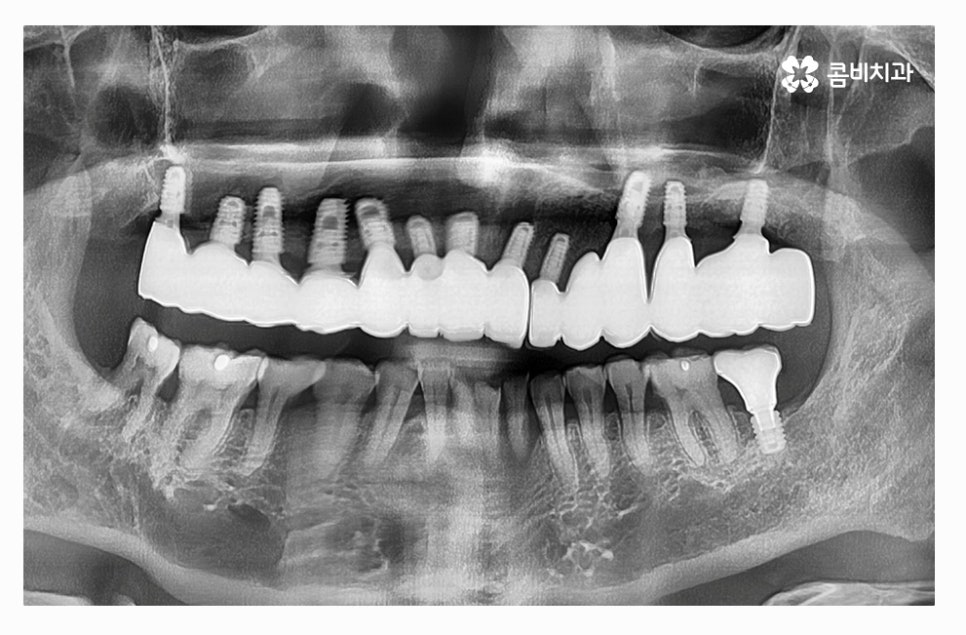

전체임플란트의 장점은 자연치아의 심미성과 매우 흡사하며

수명이 길고 저작력이 자연치아와 거의 비슷하다는 장점이 있지만

단점은 높은 비용이라고 할 수 있는데요.

전체임플란트 시술은 개개인에 따라 잇몸 상태가 다르고

식립하는 부위부터 전신 질환의 유무, 연령, 구강관리 능력과

음주 및 흡연 등에 따라서 수명이 달라질 수 있는데요.

임플란트의 치료 기간은 개개인의 잇몸과 구강 상태 등에 따라

다르며 임플란트와 잇몸 뼈가 튼튼하게 결합이 돼야 하기 때문에

빠르고 저렴한 방법이 우선시 되기보다는 개개인의

건강 상태를 충분히 고려하고 정품 사용은 기본이며

전체임플란트 수명을 오랫동안 유지하도록 치과 선택에

있어서도 믿고 찾을 수 있는 치과를 선택할 필요가 있어요.